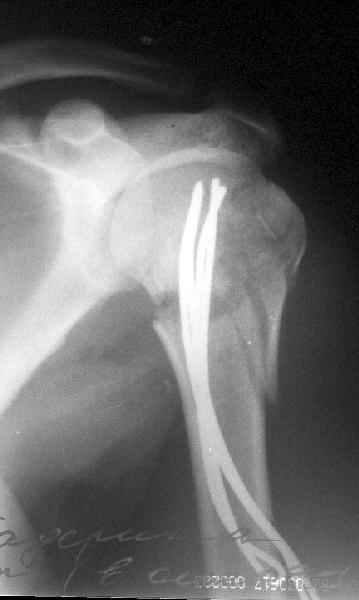

Re: Перелом шейки плеча

Да. У нас довольно скромный опыт такого остеосинтеза (по 2 случая - плечо и наружная лодыжка), дошли до использования самого простецкого троакара, через который мы сверлим кость и вводим 6 мм стержни, когда накладываем аппарат. Соответственно, в качестве забойника отлично работает любой стержень от аппарата Илизарова. Еще из наших туземных особенностей - страшная любовь к спицевым дистракторам, поэтому делали в нем. Результат у этой дамы неизвестен, т.к. она из области и уехала рожать сразу после остеосинтеза, сейчас прошло больше 5 месяцев...

Что-то, наверно, сделали мы не совсем оптимально, поскольку у Анатолия Федровича и его соратников как-то красивее "раскрываются" спицы в головке плеча - надеюсь, он прокомментирует и подскажет, что надо подправить.